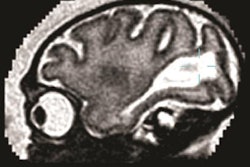

However, the diagnosis of microcephaly via ultrasound can be complex, according to SMFM. As a result, the society has developed recommendations on how to interpret the findings and when to perform follow-up ultrasound. In addition, it has provided a table of values that define the lower limit of normal for each week of pregnancy.